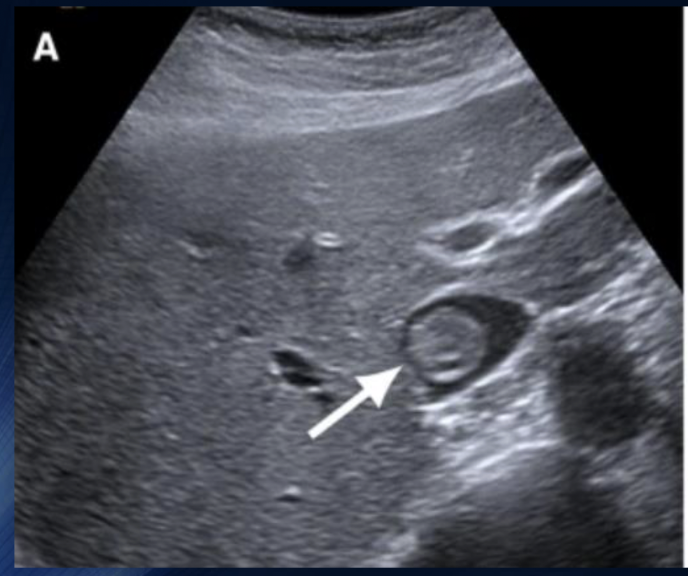

Pathology?

IVC Thrombosis